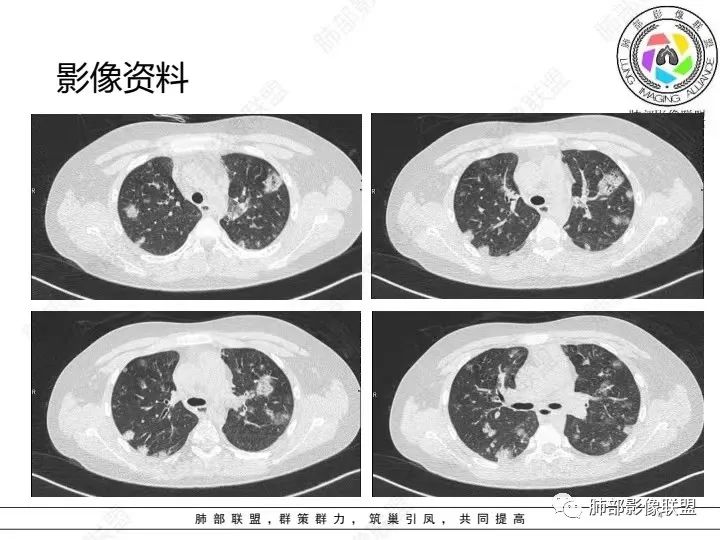

【病例】血源性金黄色葡萄球菌性肺炎1例CT影像

1.男性少年儿童,外伤后髋部疼痛,畏寒发热、咳嗽、呼吸困难。

休克血压。CRP、PCT明显升高。血气为代谢性酸中毒、呼吸性碱中毒。

2.影像上肺多发混合密度片影,随机分布,胸膜下分布优势,病灶边界大多隐约可辨,偏柔和,动脉血管影穿行,未见钙化、液化空洞、或明确气囊影,未见树芽征。

3.双侧胸腔未见积液。双肺门及纵隔未见增大淋巴结。

4.肝左右叶密度减低,未见结节影、块影或液化区。